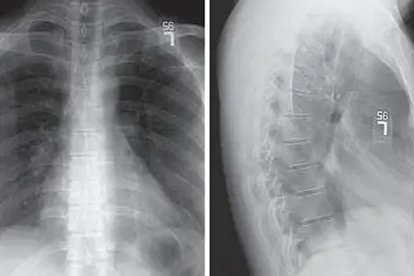

轻度压缩性骨折可采取绝对卧床休息4-6周,期间避免脊柱负重。使用硬板床并保持脊柱轴线位,配合轴向翻身预防压疮。适用于稳定性骨折且压缩程度小于椎体高度30%的患者,需定期复查X线观察愈合情况。

定制胸腰骶矫形器可提供外部支撑,限制脊柱活动6-8周。适用于能耐受支具压迫且无神经症状的中度骨折,需每日佩戴20小时以上。需注意观察皮肤受压情况,配合腰背肌等长收缩训练维持肌力。

经皮椎体成形术通过骨水泥注入稳定骨折,适用于骨质疏松性骨折伴持续疼痛。手术创伤小且恢复快,但需排除椎管内占位等禁忌证。术后24小时即可在支具保护下离床活动。